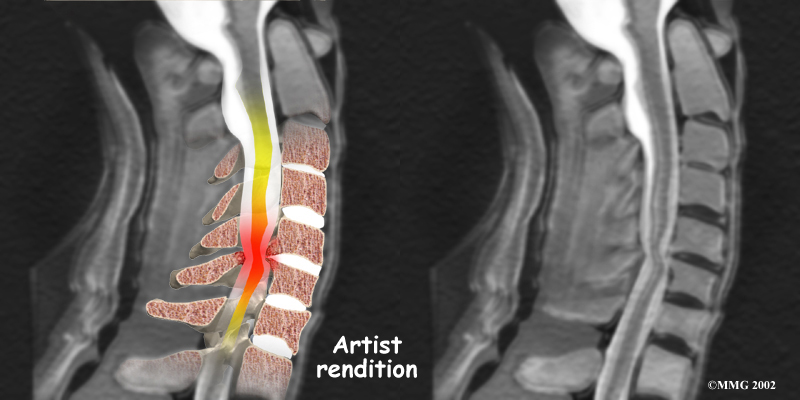

Stenosis means closed in. Spinal stenosis refers to a condition in which the spinal cord is closed in, or compressed, inside the tube of the spinal canal. Spinal stenosis may be caused by degenerative changes, such as bone spurs pushing against the spinal cord within the spinal canal.

Spinal Stenosis

However, stenosis can also develop when a person of any age has a disc herniation that pushes against the spinal canal. When the spinal cord is squeezed in the neck, doctors call the condition cervical myelopathy. This is an alarming condition that demands medical attention. Cervical myelopathy can cause problems with the bowels and bladder, change the way you walk, and affect your ability to use your fingers and hand.

Cervical Myelopathy